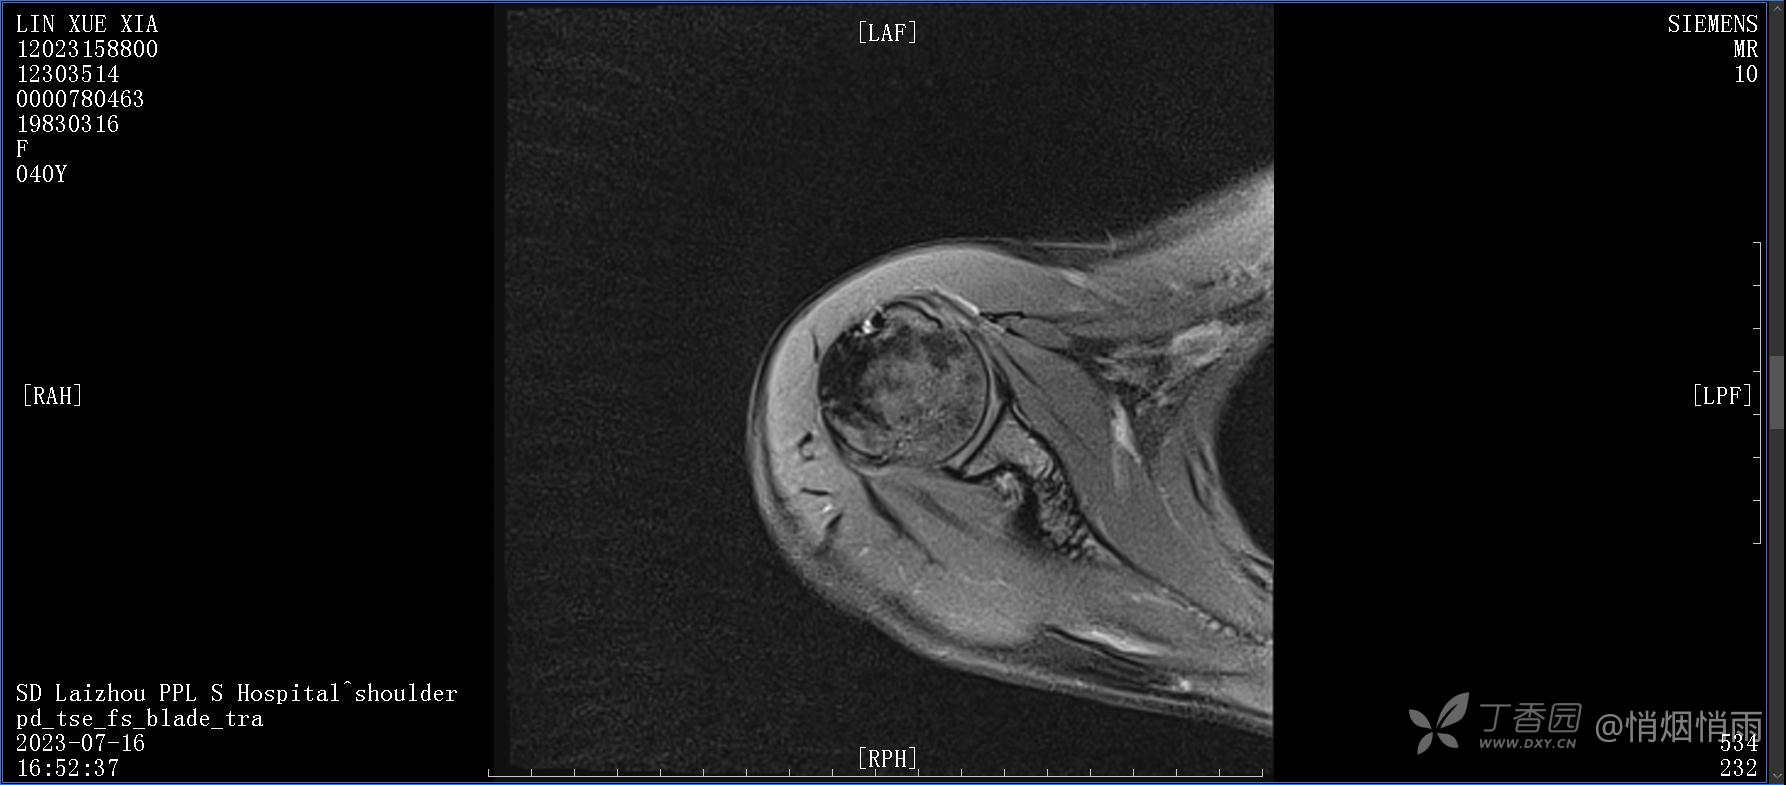

查体:右肩关节局部轻度肿胀,肩胛区压痛明显,痛处不固定,肩关节痛性活动受限,jobe test(+),lift -off test(+),中指、环指感觉较余指减退,余肢端感觉及血运情况可。

目前的诊断,暂时依据辅助检查诊为肩袖损伤,但是患者疼痛的性质和特点,却不是单纯的肩袖损伤所致。考虑过胸廓出口综合征,但是该疾病会出现肩胛区的疼痛吗?(由于考虑到费用的问题,没再进行下一步的检查)带状疱疹会有如此的症状吗?